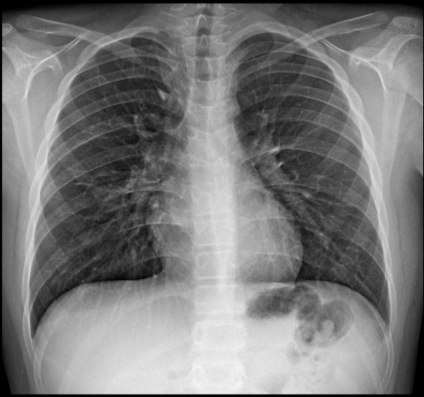

การบริการตรวจมวลกระดูก เป็นการตรวจความหนาแน่นของมวลกระดูก (Bone Mineral Density หรือ BMD) ด้วยเครื่องตรวจ DEXA Scan (Dual Energy Xray Absorptiometry Scan) เป็นเครื่องตรวจวัดความหนาแน่นของมวลกระดูก โดยใช้ X-ray พลังงานต่ำ 2 พลังงานในการตรวจ ผู้รับการตรวจจะได้รับปริมาณรังสีน้อย ซึ่งปริมาณรังสีที่ได้รับในแต่ละครั้งของการตรวจจะน้อยกว่าการตรวจ X-ray ปอดปกติทั่วไป โดยเป็นวิธีที่มีความแม่นยำสูงและถูกกำหนดให้เป็นวิธีมาตรฐานที่ใช้ในการวินิจฉัยโรคกระดูกพรุน โดยองค์การอนามัยโลก (WHO)

การเตรียมตัวก่อนการตรวจ

• ผู้รับการตรวจควรแจ้งแพทย์หรือนักรังสีเทคนิค หากสงสัยว่าตั้งครรภ์ ซึ่งการตรวจนี้จะไม่ทำการตรวจในหญิงตั้งครรภ์

• ผู้รับการตรวจควรปรึกษาแพทย์ หากเคยได้รับการกลืนแร่หรือได้รับสารทึบแสง เพื่อทำ CT scan มาก่อน ซึ่งอาจจะต้องเลื่อนการตรวจออกไปประมาณ 2 สัปดาห์

• ในวันตรวจสามารถรับประทานอาหารและน้ำได้ปกติ

ขั้นตอนการตรวจ

• ผู้รับการตรวจเปลี่ยนเสื้อผ้า ถอดอุปกรณ์ที่เป็นโลหะ หรือพลาสติกออกจากร่างกาย และนอนลงบนเครื่องตรวจ

• ใช้เวลาในการตรวจประมาณ 20-30 นาที

เครื่องตรวจความหนาแน่นมวลกระดูกแบบ DEXA BMD แบ่งเป็น 4 ส่วน คือ

1. Forearm ตรวจกระดูกแขน

2. Hip ตรวจสะโพก

3. Spines ตรวจกระดูกสันหลัง

4. Whole Body ตรวจทั้งร่างกาย